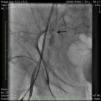

An angiogram from the left femoral sheath at this time showed retrograde filling of the distal and proximal SFA (Figure 4) and then the dissection plane in the EIA with a wire tip perforation and bleeding (Figures 5 and 6) to the retroperitoneal region at the external iliac artery with displaced bladder (Figure 6). Protamine was given to reverse the heparin and a 7-minute balloon inflation was performed in the distal SFA using a 5.0 mm×40 mm Evercross balloon (ev3, Plymouth, MN) to stop the retrograde bleeding. On repeat angiography, the distal SFA CTO was reoccluded and the dissection plane appeared to be sealed, with no further bleeding into the retroperitoneal region (Figures 7 and 8). Other than mild nausea after protamine, the patient reported no major symptoms during this procedure. When activated coagulation time was 130 s, the femoral and popliteal sheaths were removed. A 3-g/dl drop in hemoglobin was noted after the procedure that remained stable over the next two days. Popliteal and pedal pulses were palpable and unchanged following the procedure.